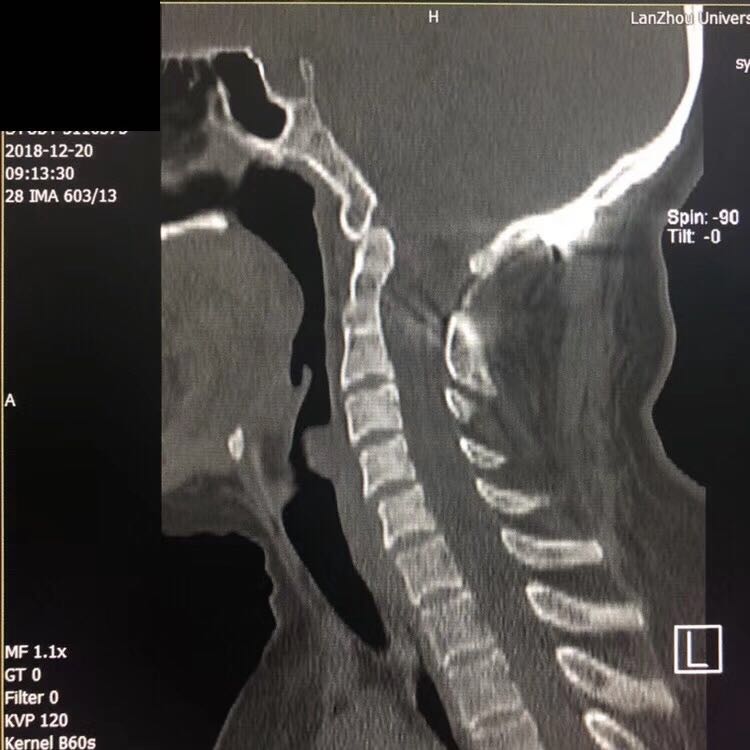

该患者为陈旧性难复性寰枢椎脱位。术前因为脱位的齿状突压迫脊髓,造成小脑扁桃体疝、脊髓空洞。四肢麻木无力无法行走。目前国际先进技术可以直接通过寰枢椎后路松解侧块关节,但这一区域紧密毗邻椎动脉、延髓呼吸中枢,稍有不慎即可造成致命后果,国内仅少数几家大医院的顶尖脊柱外科掌握此技术。